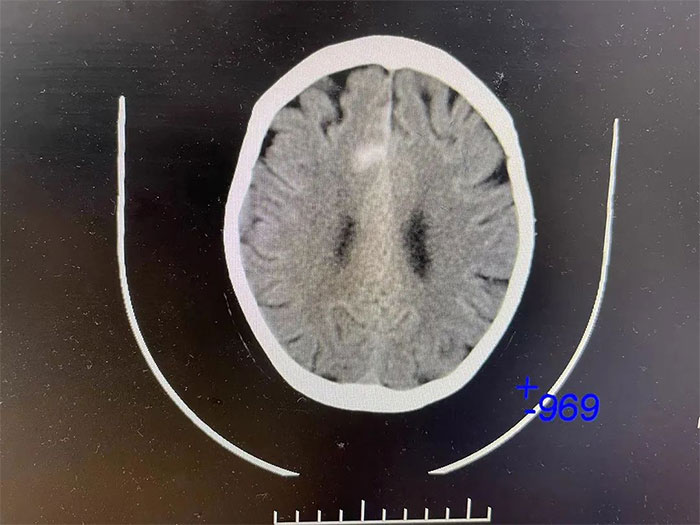

▲ 入院檢查顱內(nèi)仍有出血活動

更令人不安的是,CT檢查顯示,吳阿姨右側(cè)大腦頂葉出血灶較前變化不明顯,提示仍有出血活動,若不及時進(jìn)行干預(yù),隨時都有“決堤”的可能,不僅影響神經(jīng)功能恢復(fù),病情還可能因之進(jìn)一步惡化,甚至危及生命。